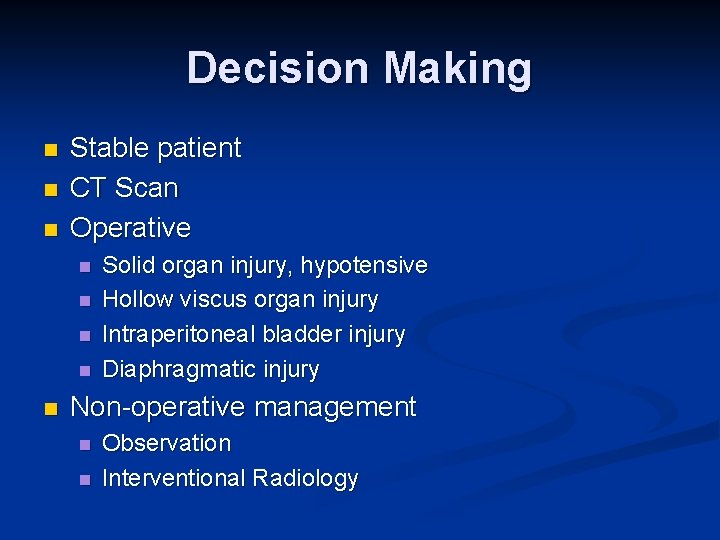

Decision Making n n n Stable patient CT Scan Operative n n n Solid organ injury, hypotensive Hollow viscus organ injury Intraperitoneal bladder injury Diaphragmatic injury Non-operative management n n Observation Interventional Radiology

Learning Points Case #2 CT scan is helpful for decision making in a stable patient n Poor detection of hollow viscus, pancreatic and diaphragmatic injury n Be worried of free fluid in abdomen n Repeat CT Scan and close clinical observation n